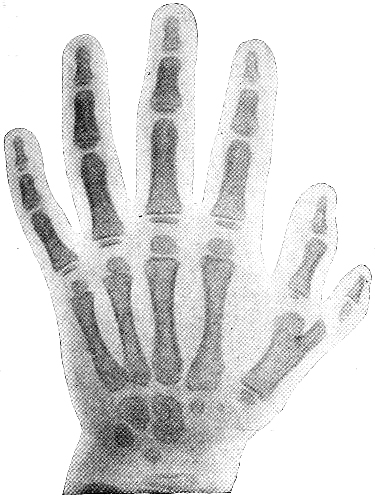

IN THE HYBRIDS

| ♂ germ- cells |